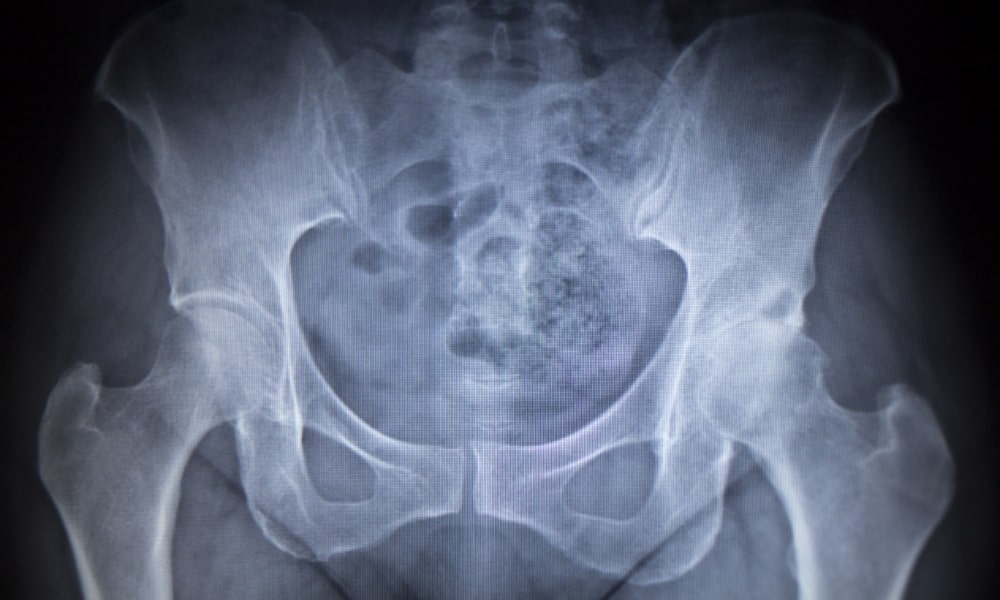

座るとお尻が痛い場合の変形性股関節症

年齢的な変化で起こりやすい変形性股関節症も、座るとお尻が痛いという症状を訴えることがあります。

整形外科や病院でレントゲンを取り変形性股関節症と診断された場合、痛みが出る方のお尻に荷重がかからないような工夫も必要となります。